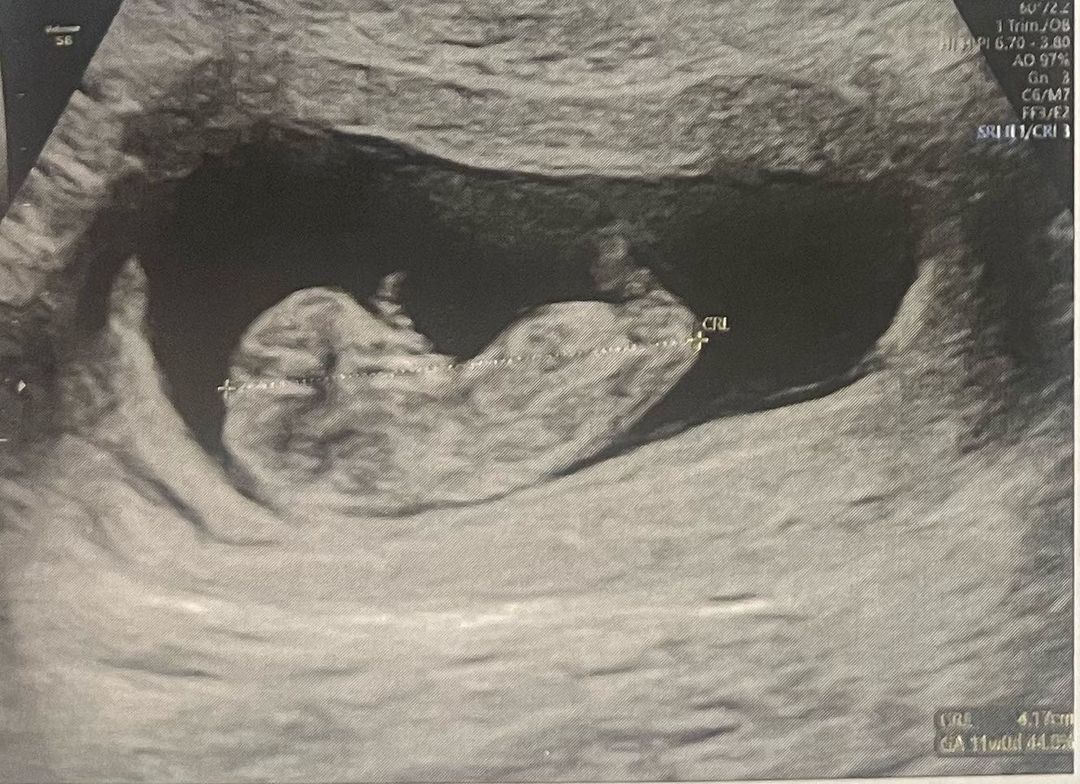

Just needed a closeup on this holiday gift..♥️ thank you for celebrating some of the greatest moments with me x

For me making a life is like making a record. you put, love joy and passion into guiding this bit of magic into arriving at what or who something greater than us decides it’s meant to be. Blood, sweat and tears go into using every ounce of yourself to avoid compromise its purity and falling short on protecting it from the world and the wounded side of yourself. You do your best because none of us are perfect but with that effort they may become something or someone that changes the world or one person for the better and the joy, fulfillment you feel is like landing on a masterpiece. Happy holidays 🎄#morelife